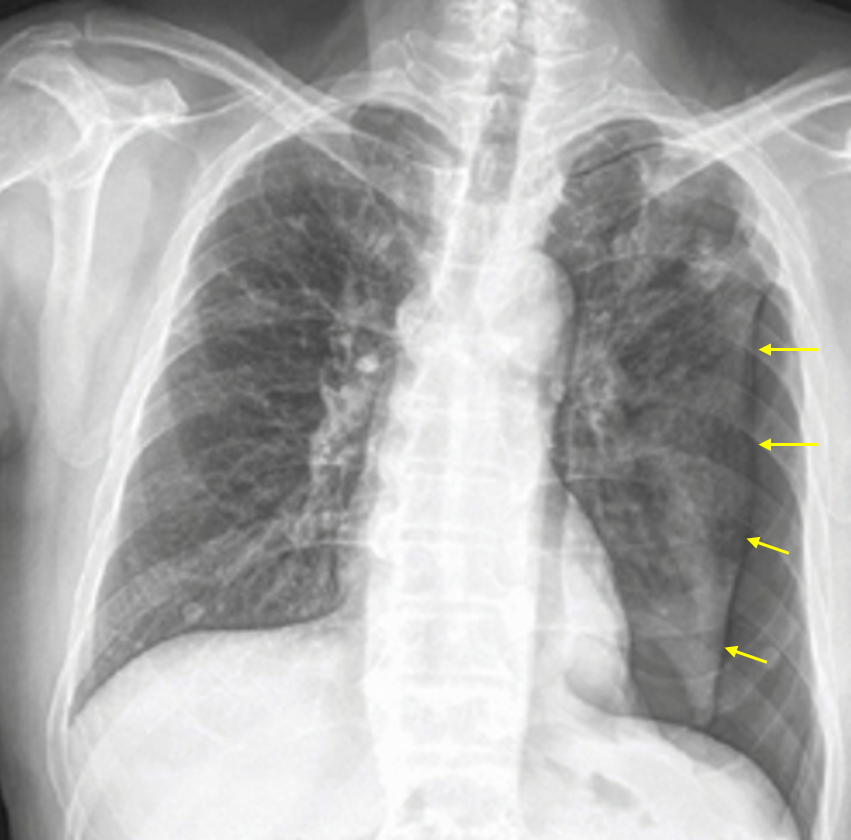

62세 남자가 2일 전부터 숨이 차고 가슴이 아파서 병원에 왔다. 걸으면 숨이 더 찼고, 숨을 깊게 들이마시거나 기침을 하면 왼쪽 가슴이 더 아팠다. 20년 전 결핵치료를 받았다. 15갑·년 과거 흡연자이다. 혈압 120/74mmHg, 맥박 90회/분, 호흡 24회/분, 체온 36.0℃이다. 가슴 청진에서 심음은 정상이나, 왼쪽 호흡음은 잘 들리지 않는다. 가슴 X선 사진이다. 혈액검사 결과는 다음과 같다. 가능성이 큰 진단을 고르시오 (한 가지).

Img | CXR: 좌측 폐 pleural line |

• 급성 좌측 흉통(들숨 때 통증 심함)과 호흡곤란, 그리고 왼쪽 가슴의 호흡음 감소에서 기흉이 의심된다.

• CXR에서 좌측 폐에 pleural line이 보이므로 기흉으로 진단할 수 있다.

검사소견 | • CXR: Pleural line 보임, vascular marking이 보이지 않음 |